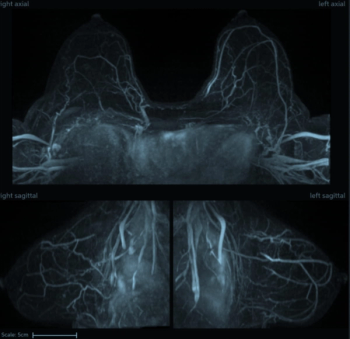

In a recent lecture at the Society of Breast Imaging (SBI)/American College of Radiology (ACR) conference, Linda Moy, MD, reviewed key tips for optimizing magnetic resonance imaging (MRI) of the breast.